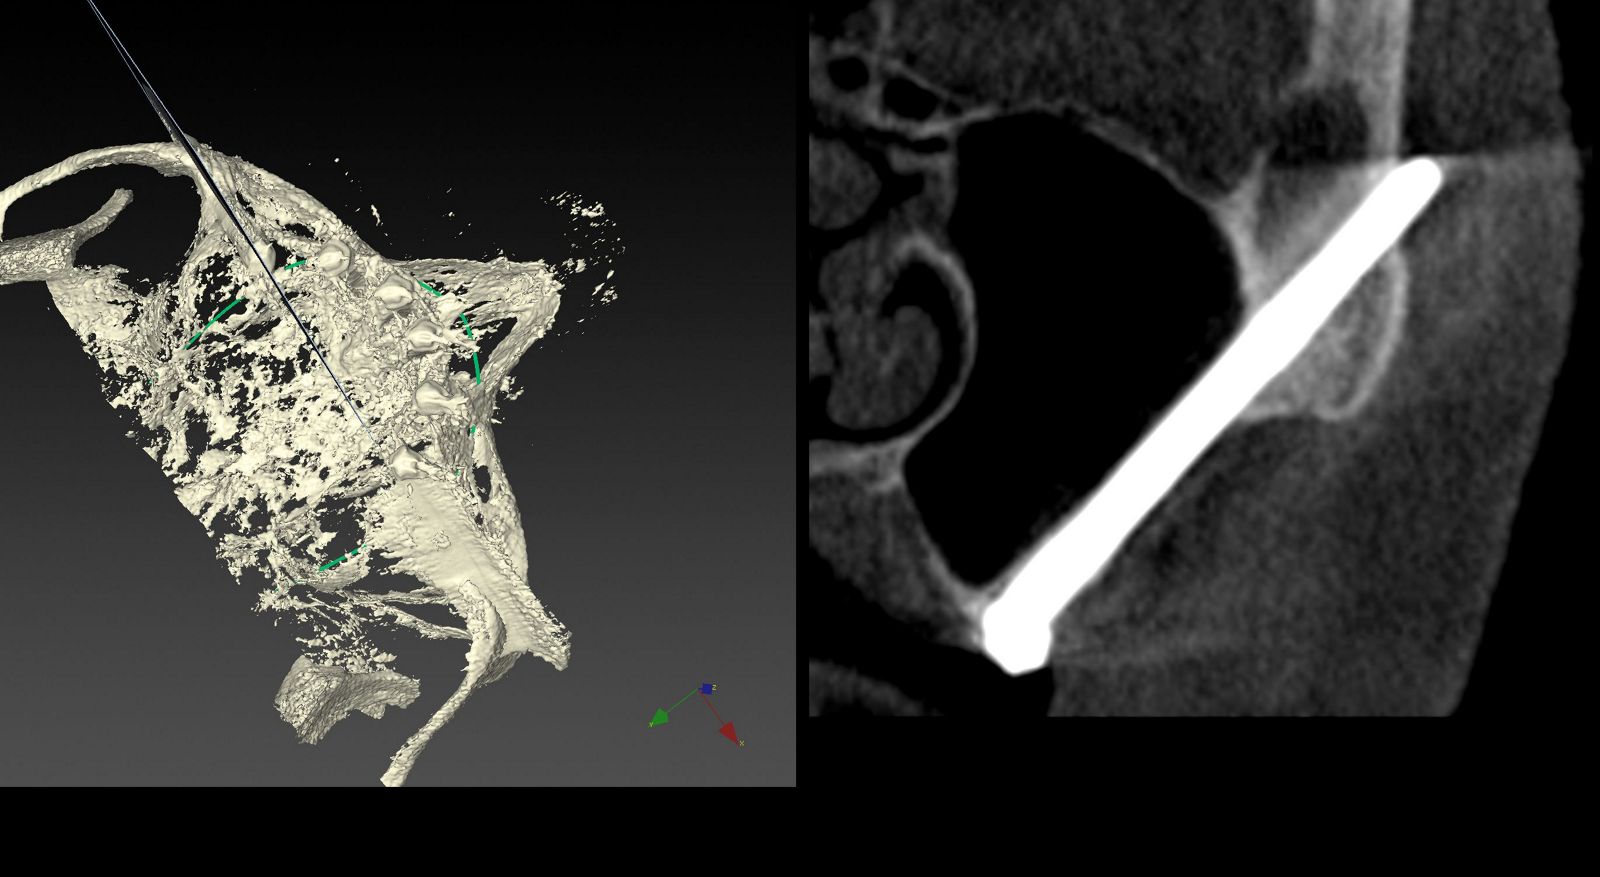

Планування операції